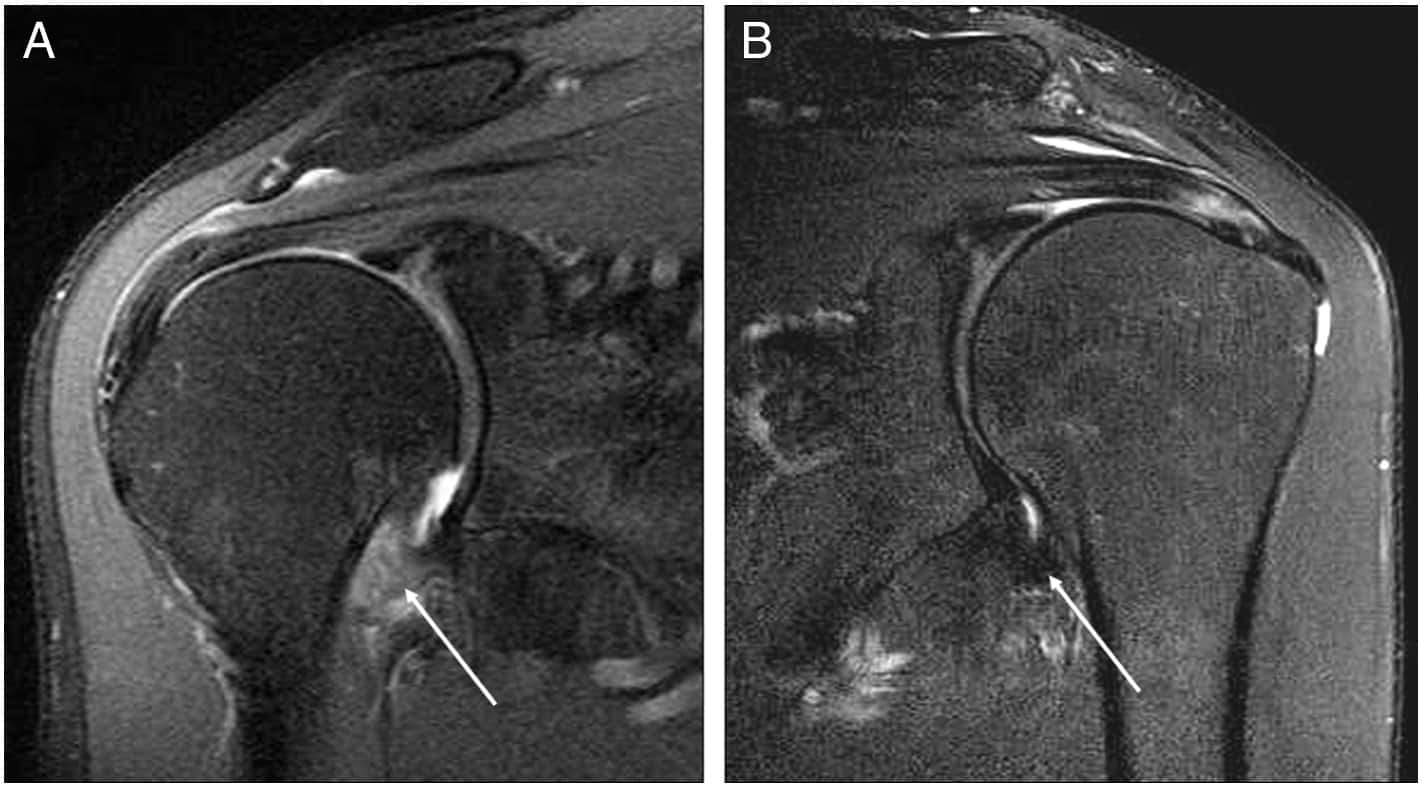

Ressonância magnética do ombro – Capsulite Adesiva

A ressonância magnética avalia o intervalo dos rotadores e o recesso axilar, que são locais comumente afetados pela capsulite adesiva.

Os achados de ressonância magnética que sugerem capsulite adesiva incluem espessamento dos tecidos moles no intervalo dos rotadores, que pode envolver os ligamentos coracoumeral e glenoumeral superior, e espessamento dos tecidos moles adjacentes à origem do bíceps.